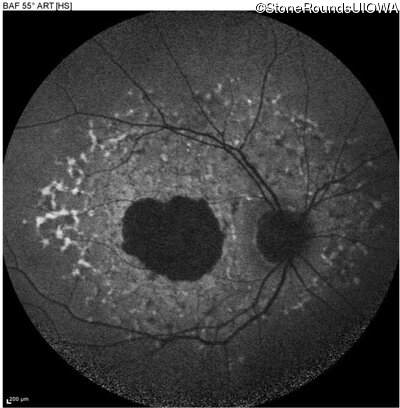

Blue Autofluorescence - Left - 20/125

Exemplar